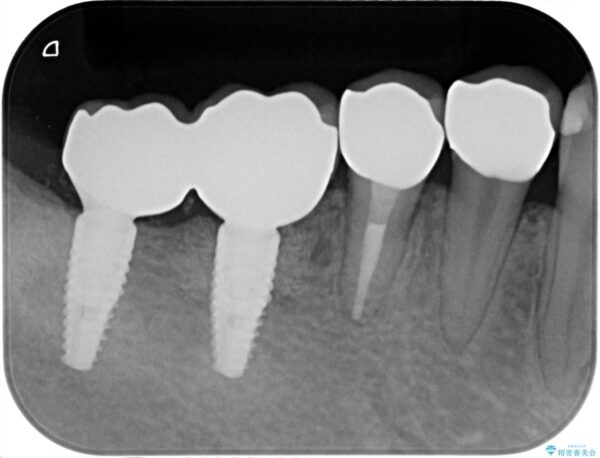

X線写真検査より、クラウンや銀歯の下で歯に大きな虫歯が発生し、抜歯を余儀なくされる状況でした。

虫歯に伴い歯槽骨の吸収も見られたので造骨後、インプラントを用いて咬合機能を回復します。

治療前

遊離歯肉移植術を伴うインプラント治療 治療前画像 遊離歯肉移植術を伴うインプラント治療 治療前画像 遊離歯肉移植術を伴うインプラント治療 治療前画像 遊離歯肉移植術を伴うインプラント治療 治療前画像 遊離歯肉移植術を伴うインプラント治療 治療前画像 遊離歯肉移植術を伴うインプラント治療 治療前画像 遊離歯肉移植術を伴うインプラント治療 治療前画像 遊離歯肉移植術を伴うインプラント治療 治療前画像 遊離歯肉移植術を伴うインプラント治療 治療前画像